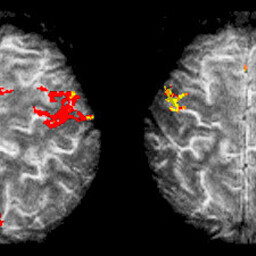

14.01.16 NOORTEADLASED ... Magnetresonantstomograafia uuring võimaldab meil inimkehast teha pildi, kuid see võtab aega ning seda aega tihtilugu pole. Kuidas saada MRT pilt kiiresti ja kvaliteetselt, sellele on võimalik lahendus matemaatikute ja füüsikute kätes.